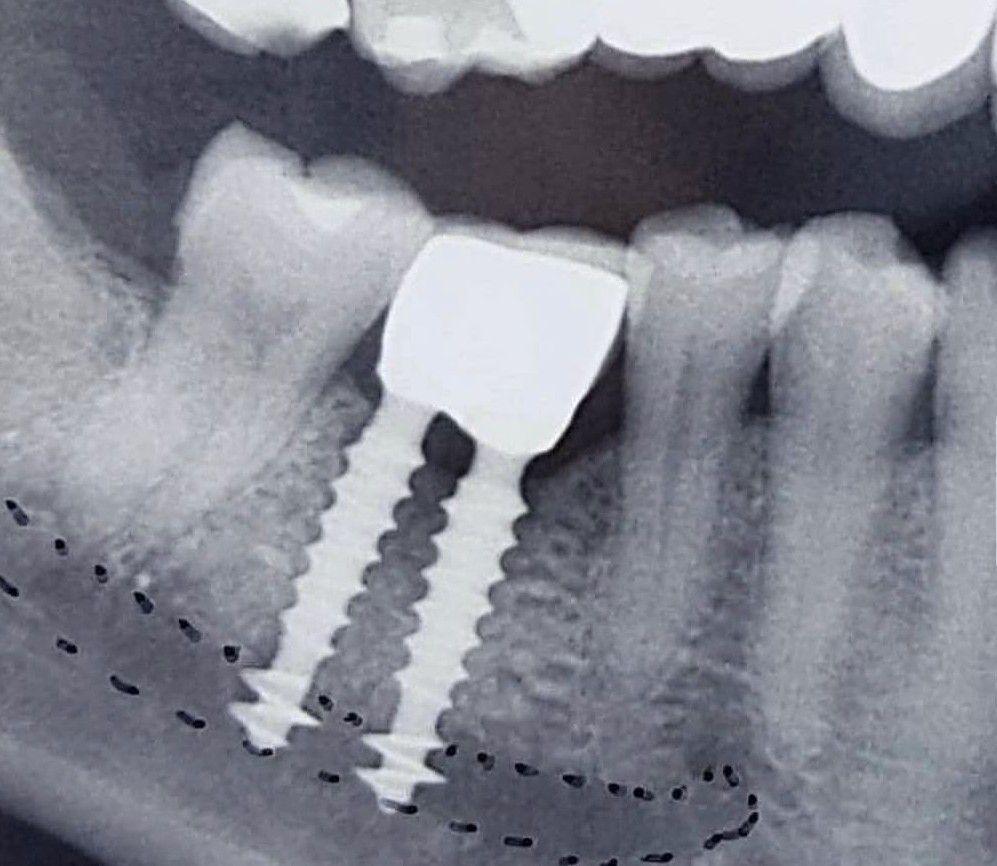

Implant Failure

Can you guess what has gone wrong here?